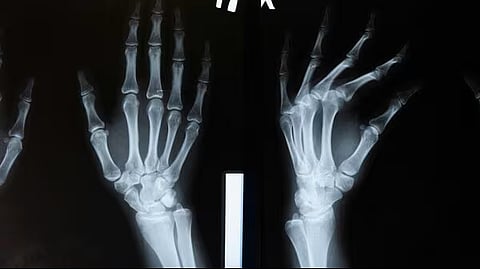

أعلن فريق بحثي في مقاطعة تشيجيانغ شرق الصين، تطوير "غراء عظمي" جديد باسم Bone-02، قادر على تثبيت الشظايا العظمية المكسورة خلال ثلاث دقائق فقط، في خطوة وُصفت بأنها "اختراق علمي" في جراحة العظام.

ويتميز Bone-02 بسرعة التثبيت ودقته حتى في بيئة غنية بالدم، إضافة إلى كونه قابلاً للامتصاص داخل الجسم أثناء الالتئام، ما "يلغي الحاجة لعمليات لاحقة لإزالة المسامير أو الصفائح"، وفق الفريق.

وأظهرت الاختبارات المعملية سلامة وفعالية المادة؛ ففي تجربة، أُنجزت الجراحة في أقل من 180 ثانية، مقارنة بالوقت الأطول المطلوب لزرع الصفائح والمسامير التقليدية.

وبحسب النتائج، حقق الغراء قوة ربط تفوق 400 رطل، وقوة قص تبلغ نحو 0.5 ميغاباسكال، وقوة ضغط تقارب 10 ميغاباسكال.

كما أفادت التجارب السريرية على أكثر من 150 مريضاً بنتائج ناجحة، ما يعزز إمكانية أن يصبح بديلاً للزراعات المعدنية المتعارف عليها، مع احتمال تقليل مخاطر العدوى.